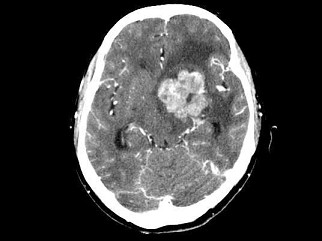

男,42岁,头痛、恶心半年余,逐步加重,右侧肌力减弱,CT检查如图,最可能的诊断是()

A.脑膜瘤

B.胶质瘤

C.转移瘤

D.畸胎瘤

E.室管膜瘤

男,42岁,头痛、恶心半年余,逐步加重,右侧肌力减弱,CT检查如图,最可能的诊断

[单选题]男,42岁,头痛、恶心半年余,逐步加重,右侧肌力减弱,CT检查如图,最可能的诊断是()A . 脑膜瘤B . 胶质瘤C . 转移瘤D . 畸胎瘤E . 室管膜瘤